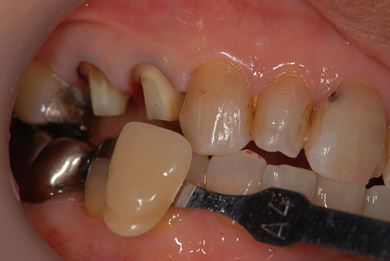

| 主訴 | 痛む歯を治療し、セラミックの歯にしたい。 | ||||||||||||||||||||||||||||||||

| 治療内容 | メタルボンドセラミック2本(メタルボンドセラミッククラウン用の土台2本)、ハイブリッドセラミックインレー2本 | ||||||||||||||||||||||||||||||||